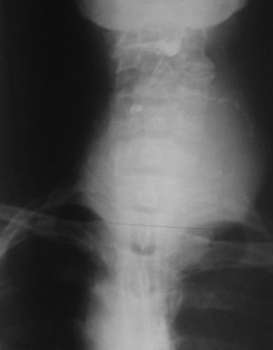

Rx toracică, incidență P-A

DESCRIERE:

la niv. întregului hemitorace drept → opacitate extinsă, nesistematizată, de intensitate mare, omogenă

caracter expansiv → împinge traheea și mediastinul de partea opusă

diafragm deplasat în jos

lărgirea spațiilor intercostale

umplerea spațiului costo-diafragmatic

DX: pleurezie masivă

DD: atelectazie → caracter retractil